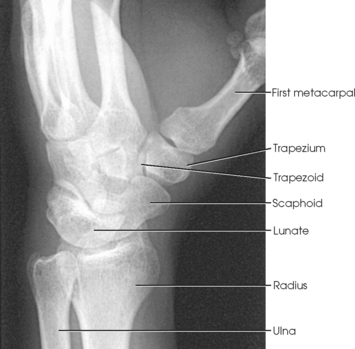

The wrist has eight carpal bones, which are fitted closely together and arranged in two horizontal rows (see Fig. 4-1). The carpals are classified as short bones and are composed largely of cancellous tissue with an outer layer of compact bony tissue. These bones, with one exception, have two or three names; this atlas uses the preferred terms (see box). The proximal row of carpals, which is nearest the forearm, contains the scaphoid, lunate, triquetrum, and pisiform. The distal row includes the trapezium, trapezoid, capitate, and hamate.

Each carpal contains identifying characteristics. Beginning at the proximal row of carpals on the lateral side, the scaphoid, the largest bone in the proximal carpal row, has a tubercle on the anterior and lateral aspect for muscle attachment and is palpable near the base of the thumb. The lunate articulates with the radius proximally and is easy to recognize because of its crescent shape. The triquetrum is roughly pyramidal and articulates anteriorly with the hamate. The pisiform is a pea-shaped bone situated anterior to the triquetrum and is easily palpated.

Beginning at the distal row of carpals on the lateral side, the trapezium has a tubercle and groove on the anterior surface. The tubercles of the trapezium and scaphoid constitute the lateral margin of the carpal groove. The trapezoid has a smaller surface anteriorly than posteriorly. The capitate articulates with the base of the third metacarpal and is the largest and most centrally located carpal. The wedge-shaped hamate exhibits the prominent hook of hamate, which is located on the anterior surface. The hamate and the pisiform form the medial margin of the carpal groove.

The carpals articulate with each other, the metacarpals, and the radius of the forearm. In the carpometacarpal (CMC) articulations, the first metacarpal and trapezium form a synovial saddle joint, which permits the thumb to oppose the fingers (touch the fingertips). The articulations between the second, third, fourth, and fifth metacarpals and the trapezoid, capitate, and hamate form synovial gliding joints. The intercarpal articulations are also synovial gliding joints. The articulations between the lunate and scaphoid form a gliding joint. The radiocarpal articulation is a synovial ellipsoidal type. This joint is formed by the articulation of the scaphoid, lunate, and triquetrum, with the radius and the articular disk just distal to the ulna (Fig. 4-9, C).